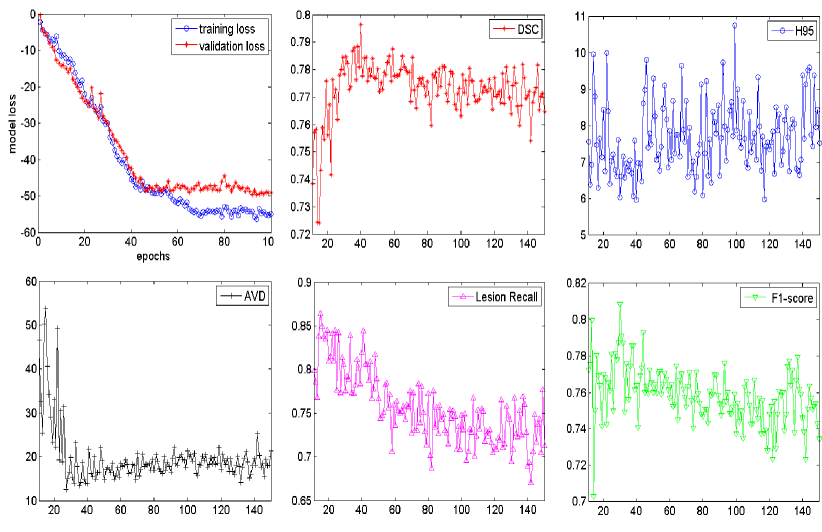

For reported results, the binary segmentation maps were evaluated using the five metrics described in Section 2: dice similarity coefficient, Hausdorff distance (95p), averaged volume difference, lesions recall and lesions F1-score. The U-Net hyper parameters were set as follows: batch size for computing the training loss was set to 30; learning rate was set to 0.0002; the number of epochs was set to 50. The number of models in the ensemble was set to 3. Section 5.2 further evaluates and analyses the effects of some key parameters on segmentation performance.

We selected the number of epochs for stopping training by contrasting training loss and validation loss over epochs. We split the public training dataset into a training set and a validation set by randomly picking 80% and the remaining 20% cases from each scanner respectively. Thus in total, the models were trained on 48 cases and validated on 12 cases. Figure 9 shows the curves of training and validation loss over 100 epochs. It could be observed that the validation loss did not show a descending trend at around 50 epochs. The reason to choose 50 epochs rather than a higher one is 1) to avoid over fitting on the training data, and 2) keep low computational cost.

Figure 13 shows the curves of segmentation performance on five metrics w.r.t different ensemble size. It could be seen that (1) the ensemble with three or more models clearly outperformed the ensemble of only one model on all of the five metrics. The improvement of ensemble model with size over one with size is statistically significant on five metrics, all with small p-values; (2) when the size was further increased, performance tended to saturate and minor improvements in some of the measures came at the cost of small decreased in others. Figure 14 shows standard deviation of segmentation performance between five repeated trained models w.r.t different ensemble size. It could be observed that the variation of segmentation performance was reduced on the main evaluation metrics when the size of ensemble was increased. It demonstrated that the ensemble model can not only boost the segmentation performance but also guarantee a robust segmentation result. Figure 15 shows a case segmented by three individual models and their ensemble. We observed that three models trained with different weights initializations and shuffled data generated significantly different result on boundary and small lesions. And the model ensemble avoided the worst segmentation result.